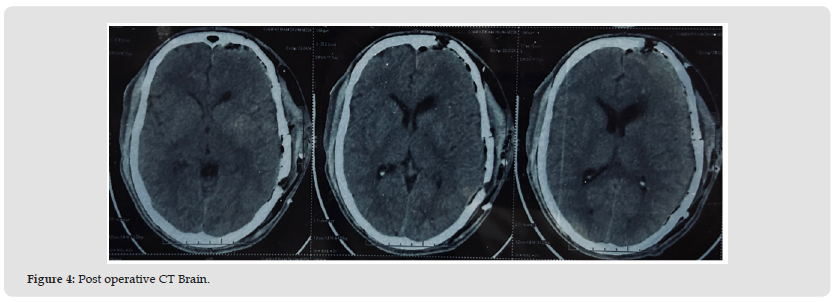

In postoperative care patient experienced sudden episode of anterior wall MI followed by 3 episodes of monomorphic VT. Episode was managed accordingly. The histopathological examination was suggestive of Glioblastoma( WHO grade 4) and molecular studies were advised to confirm the diagnosis. Review of blocks and Immunochemistry showed invasive tumor infiltrating adjacent brain parenchyma, with cells arranged as solid sheets and nests with few intervening delicate thin-walled capillary channels with brisk mitosis. Immunochemistry showed diffuse positivity for CD99, FLI-1 and NKX2.2. Tumor cells were negative for GFAP, Olig2, CD45, SALL4, NeuN, STAT6 and Chromogranin A. P53 displays wild-type expression and ATRX is retained. Ki67 proliferation index was approximately 95%. The overall features were compatible for the possibility of Ewing sarcoma. The findings of further metastatic workups, including CT scans of thorax and abdomen were negative. A postoperative CT scan of brain revealed left parietal extradural bleed of 23 x 90 mm and left frontal bleed of 4-6 mm. About 20-25 mm hemorrhagic contusions in left frontal cortex and smaller foci of pneumocephalus was present. Mass effect causing compression of left lateral ventricle was noted with a 12 mm midline shift to right (Figure 4).